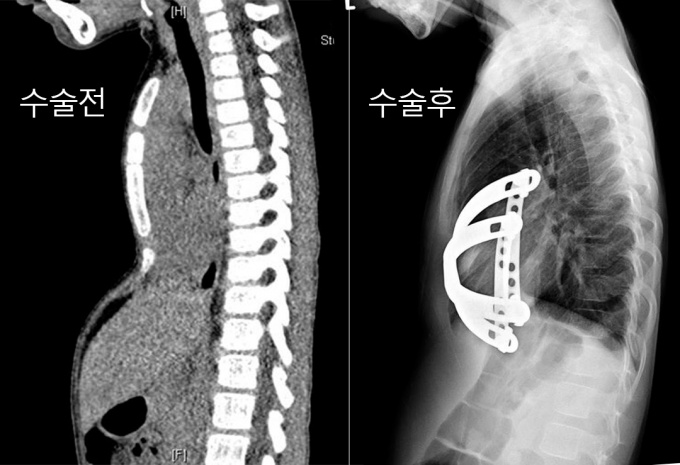

¾Æ¶ó¶ùÀº »ýÈÄ 6°³¿ùÀÌ Áö³µÀ» ¶§ ¿À¸ñ°¡½¿ Áø´ÜÀ» ¹Þ¾Ò´Ù. ¿À¸ñ°¡½¿Àº °¡½¿ÀÌ ¼±ÃµÀûÀ¸·Î °úµµÇÏ°Ô ÇÔ¸ôµÈ °¡½¿»ÀÀÇ ±âÇüÀÌ´Ù. ¿À¸ñ°¡½¿Àº Ãâ»ýºÎÅÍ ¹Ù·Î ³ªÅ¸³ª ¼ºÀå°ú ÇÔ¸ôÀÌ µ¿½Ã¿¡ ÁøÇàµÈ´Ù. ÇÔ¸ôµÈ °¡½¿Àº ½ÉÀåÀ» ´©¸£°í ¼ºÀåÇϸ鼭 ÆóÀÇ ¿ëÀûµµ ÁÙ¾îµé°Ô µÈ´Ù. À̴ ȣÈí°ï¶õ°ú ¿îµ¿±â´É ÀúÇϸ¦ ¾ß±âÇÑ´Ù.

Áö³­ 16ÀÏ ÀÔ¿ø ´ç½Ã ¾Æ¶ó¶ùÀº CT»óÀ¸·Î ³ªÅ¸³­ ÇÒ·¯Áö¼ö(HI, Haller index)°¡ 5.56¿´´Ù. Á¤»óÀÎÀÇ ÇÒ·¯Áö¼ö°¡ 2.5~2.8ÀÎ °ÍÀ» °¨¾ÈÇÏ¸é ¸Å¿ì ½É°¢ÇÑ »óÅ¿´´ø °ÍÀÌ´Ù.

ÁÖÄ¡ÀÇÀÎ ÈäºÎ¿Ü°ú À̼º¼ö ±³¼ö´Â ¾çÂÊ °Üµå¶ûÀÌ ¹Ø 2-3cm¸¦ Àý°³ÇÑ ÈÄ Æ¼Å¸´½ ±Ý¼ÓÀ¸·Î ¸¸µé¾îÁø ³Ê½º¹Ù¸¦ Èä°ñ ¹ØÀ¸·Î ³Ö¾î µé¾î°£ Èä°ñÀ» ¿Ã¸®´Â ÃÖ¼Òħ½À¼ö¼úÀÎ ³Ê½º ¼ö¼úÀ» ½Ç½ÃÇß´Ù.

Á¤µµ°¡ ½ÉÇÑ ¾Æ¶ó¶ùÀº ³Ê½º¹Ù 2°³¸¦ ³Ö¾î XÀÚ ÇüÅ·Π±³Â÷½ÃÄ×´Ù. ±³Á¤µÈ Èä°ñÀÌ ÀÚ¸®Àâ´Âµ¥ 2~3³â Á¤µµ °É¸®°í ÃßÈÄ ³Ê½º¹Ù Á¦°Å ¼ö¼úÀ» ¹Þ¾Æ¾ßÇÑ´Ù.